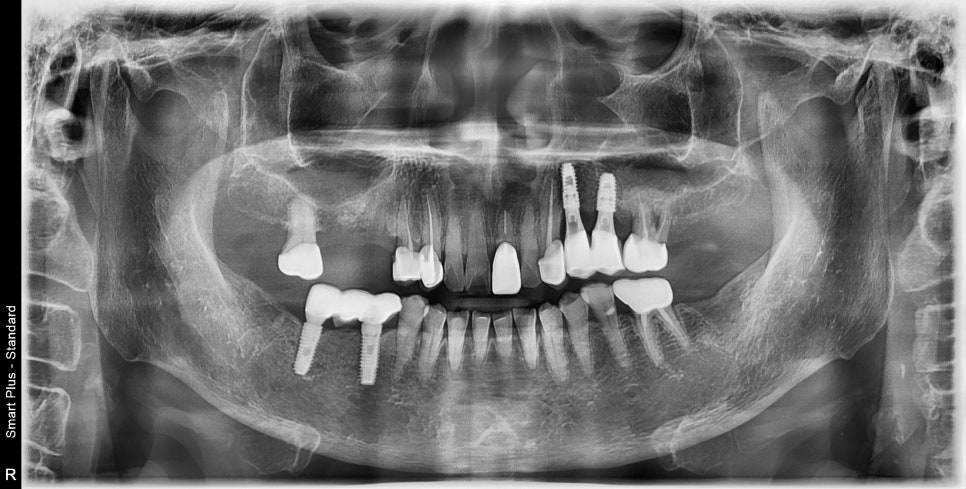

문제 부위의 발치를 한 후 수술 시기까지 기다리는 동안

반대편 치료를 완료했습니다.

기존 치아상실 부위의 임플란트 식립

기존 염증 부위가 범위가 너무 넓었기 때문에 수술을 위해서는 시간이 필요했습니다.

그 사이 왼쪽 먼저 식사를 하실 수 있게 도와드린 후

반대편 수술이 진행되었습니다.

수술을 진행하며 부족한 부위의

뼈이식을 추가로 진행하며 나머지 임플란트를 식립했습니다.

아직 염증이 있던 부위의 뼈가 약해져있기 때문에

임플란트와 뼈와 고정력이 생기기 위해서는 좀 더 시간이 필요하다고 말씀드렸습니다.